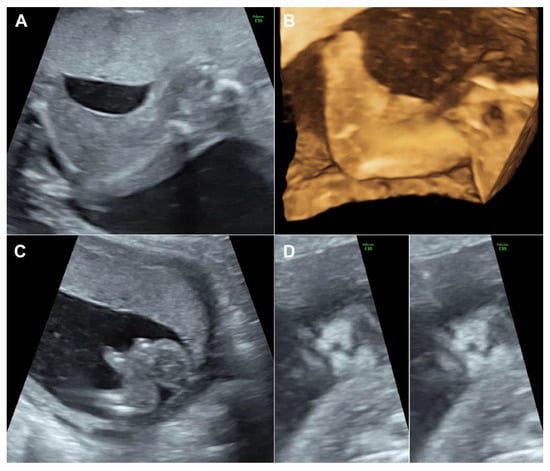

A 30-year-old pregnant woman, G3 P1011, presented for antenatal care and fetal anomaly screening at 20 weeks of gestation. She had no serious underlying medical disease, except left traumatic optic neuropathy. Also, her familial history was unremarkable. The first pregnancy ended up with miscarriage at 8 weeks of gestation. The second pregnancy gave birth to a healthy term female newborn, weighing 3550 g. The current pregnancy course was uneventful. Ultrasound examination for fetal anomaly screening at 20 week of gestation showed a single viable fetus with abnormalities as follows (Figure 1): bilateral popliteal pterygia extending from posterior aspect of the thighs to the heels with restriction in extension of both knees (no more than 90°), bilateral talipes equinovarus, syndactyly and ectrodactyly of the toes, ambiguous genitalia (penis-like phallus with poorly developed scrotum and suspected of hypospadias) and suspicious of cleft lips (variant). Biometry was consistent with gestational age (using Voluson E10 machine equipped with transabdominal 2- to 4-MHz curvilinear transducers; GE Healthcare Ultrasound, Milwaukee, WI, USA). The placenta was normal and amniotic fluid volume was normal. Both upper limbs were structurally normal and had normal movement. No other structural anomaly was identified. Fetal cord blood which was obtained by cordocentesis and parental blood samples were sent for trio whole-exome sequencing. Because of the severe abnormalities of both lower extremities and genital structures, the couple requested to have the pregnancy terminated. Therapeutic abortion was performed using transvaginal misoprostol. A male fetus with ambiguous genitalia was aborted at the 20 weeks of gestation, weighing 420 g. Postnatal findings confirmed the prenatal sonographic features (bilateral popliteal webs extending from posterior aspect of the upper thighs to the heels with bilateral talipes equinovarus, syndactyly and ectrodactyly of the toes, and ambiguous genitalia), as presented in Figure 2. The placenta was grossly normal. Fetal karyotype was 46, XY. The molecular genetic analysis by whole-exome sequencing was subsequently performed. All exon regions of all human genes were captured by xGen Exome Research Panel v2 (Integrated DNA Technologies, Coralville, IA, USA). The captured regions of the genome were sequenced with Novaseq 6000 (Illumina, San Diego, CA, USA). The raw genome sequencing data analysis, including alignment to the GRCh37/hg19 human reference genome, variant calling and annotation, was conducted with open-source bioinformatics tools and in-house software (3 billion Inc. Seoul, Seoul, Korea). The result revealed a heterozygous pathogenic variant in IRF6 (NM_0061474; c.250C > T; p.Arg84Cys) in the fetus, consistent with molecular diagnosis of Popliteal Pterygium Syndrome type 1 (MIM #119500). This condition is inherited by autosomal dominant manner. However, trio analysis in this family proves that the pathogenic variant in the affected case occurred de novo. Therefore, the recurrent risk in the next pregnancy is less than 1%. This information was provided to the couples.

The case presented here emphasizes on careful delineation of anatomical survey. Abnormal posture of the lower limbs including clubfeet (equinovarus), restriction of lower limb movement was the first clue, warranting detailed ultrasound. Actually, the well-defined popliteal pterygia can be simply missed, if not exactly midsagittal scans of the lower limbs. It is noteworthy that cross-sectional scans, oblique scans or coronal scans along the long axis view of the lower limbs cannot clearly demonstrate the popliteal webbing. The examiner must carefully identify the true midsagittal scans to clearly visualize the popliteal webbing as presented in Figure 1 and Video 1. In cases of high suspicion, 3D-ultrasound can be helpful in reconstruction to demonstrate the webbing (Figure 2). On literature review, popliteal webbing is very rarely demonstrated clearly with prenatal ultrasound. Nevertheless, since the sonographic images of extremities can be visualized in early gestation, it is, theoretically, possible that the popliteal webbing can be detected earlier in late first trimester or early second trimester. However, the diagnosis in our case, unfortunately, was detected at 20 weeks of gestation, relatively late, since we routinely perform anomaly screening at mid-pregnancy, while first trimester screening is only optional, not routine.

Figure 1. (A) Webbing from the posterior aspect of the thigh extending to the heels; (B) 3D-US reconstruction of the lower limb shows popliteal webbing; (C) Club foot shows ectrodactyly; (D) Coronal view of the fetal face shows bilateral grooves of the upper lip (left: superficial plane; right: deeper plane).